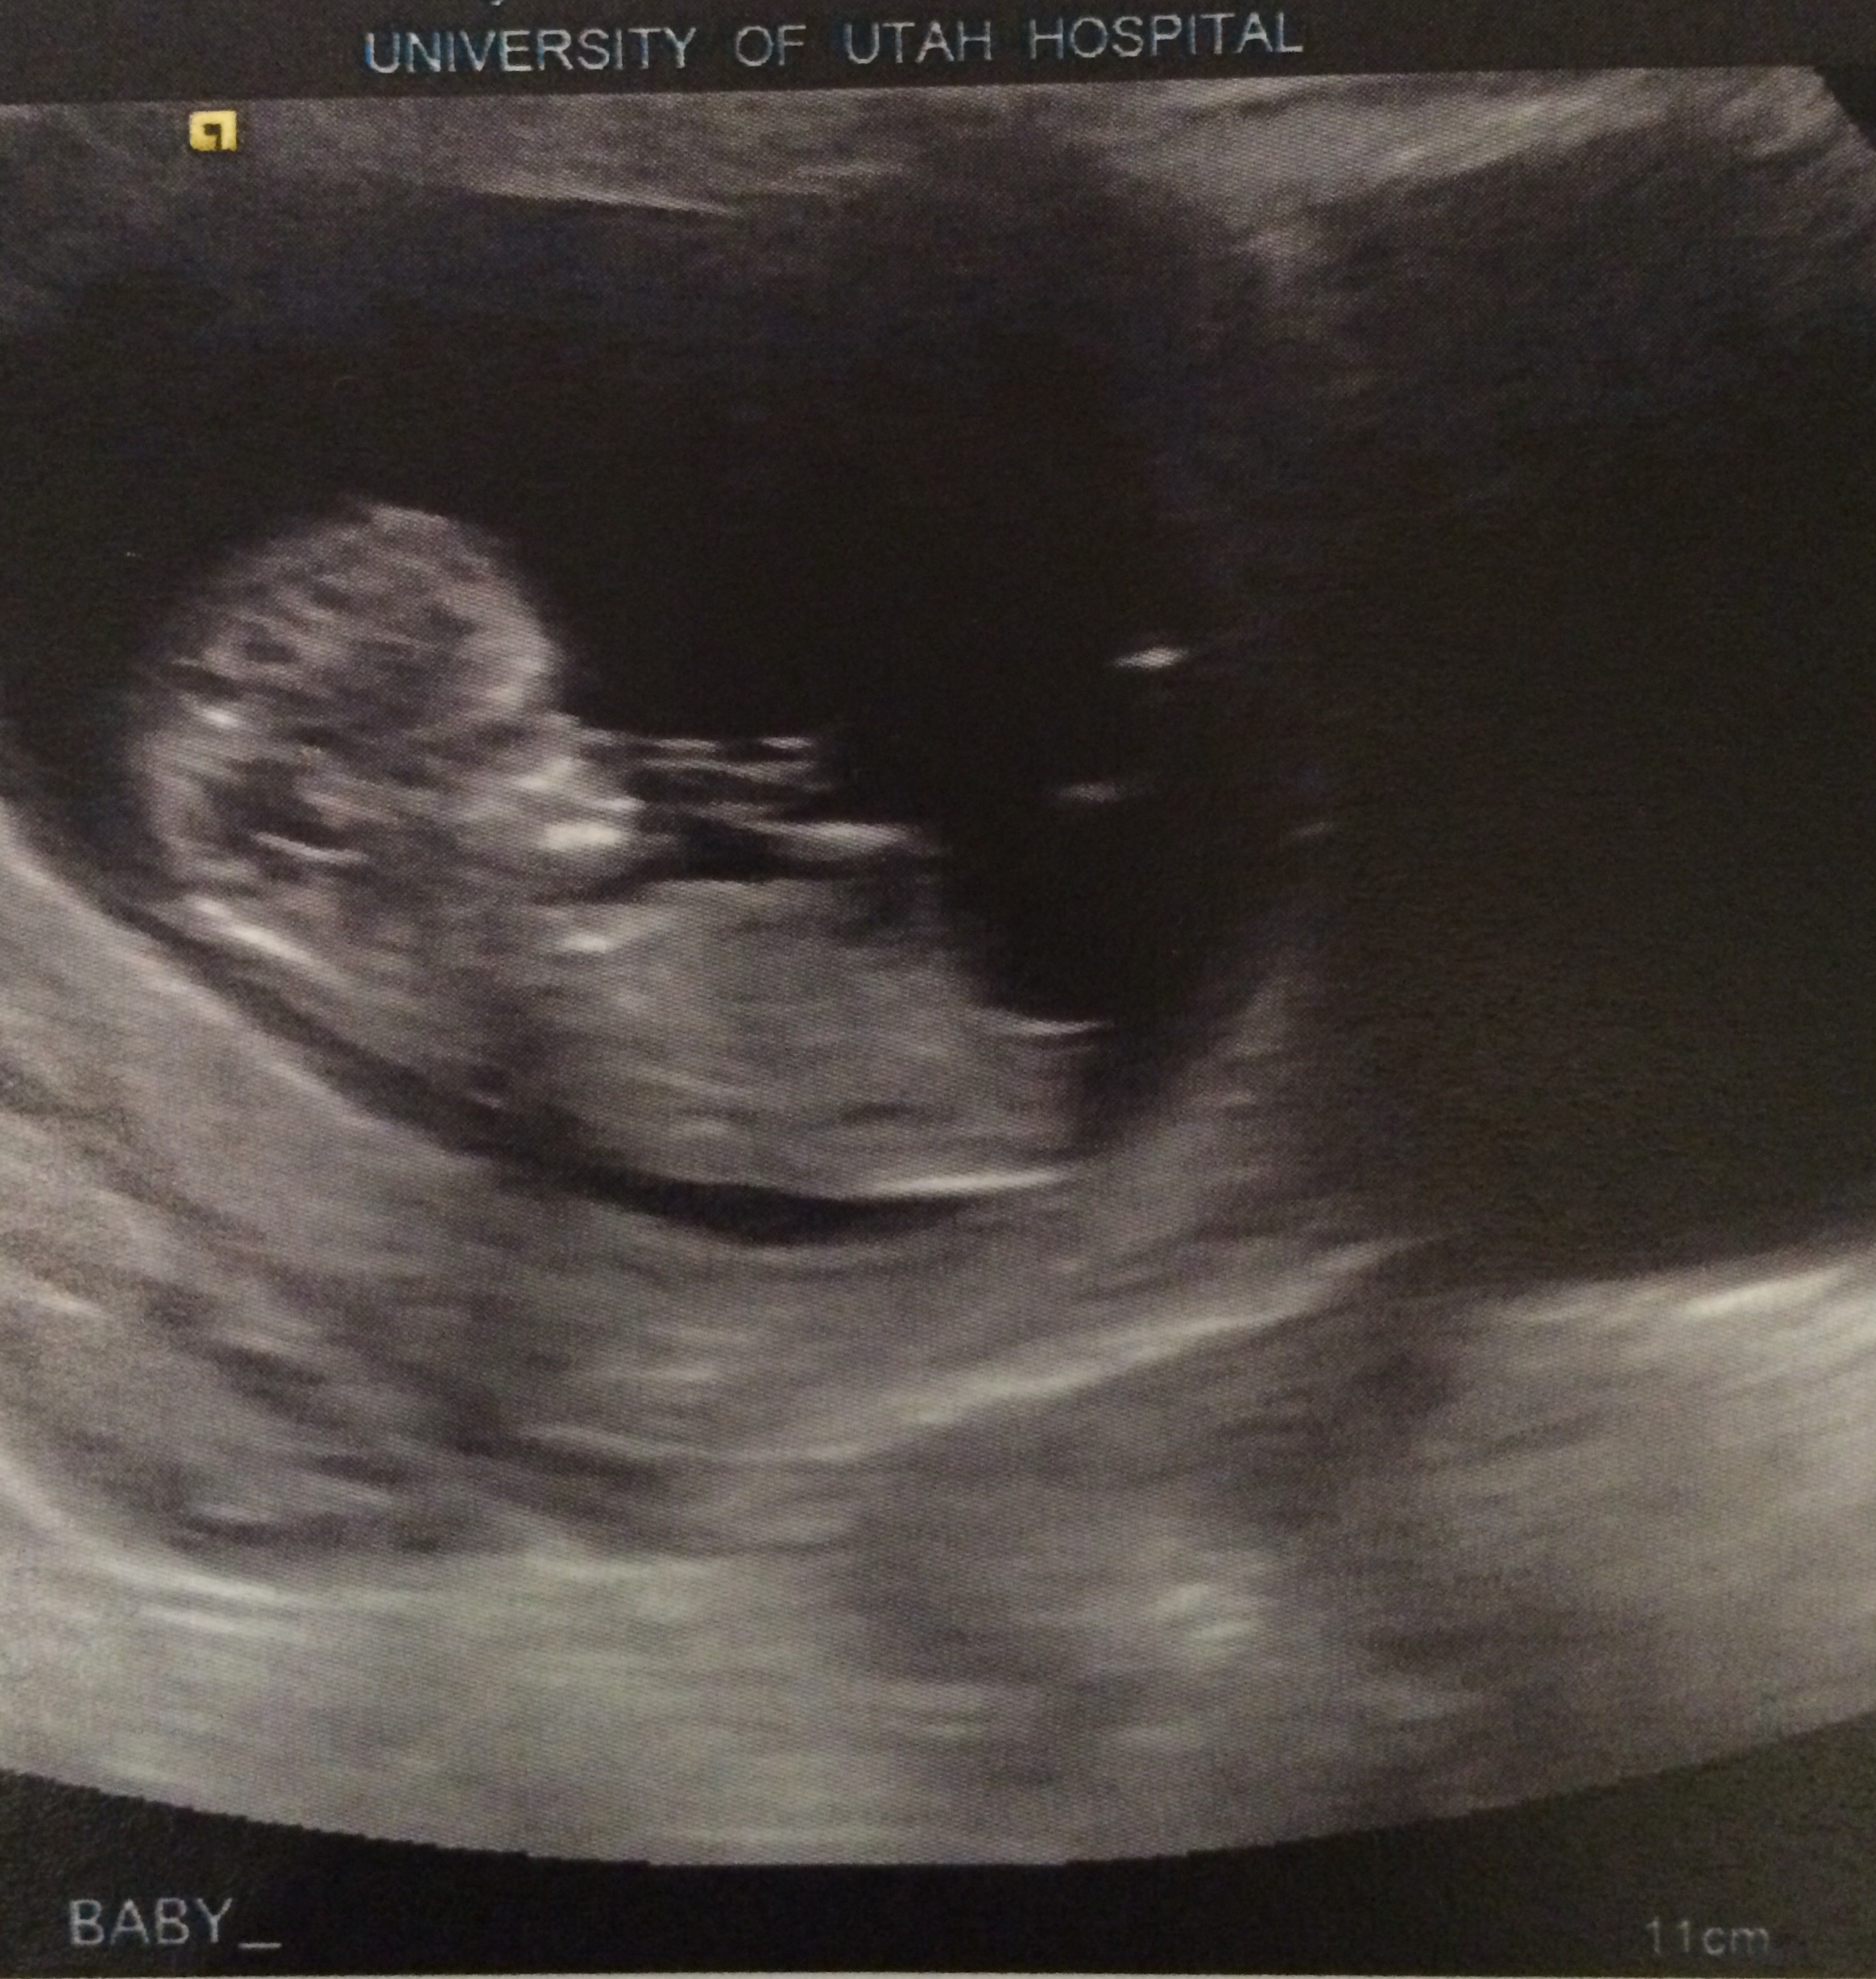

I had an ultrasound this morning because I had been cramping and spotting and the baby looked great!! It was measuring at 12w1d and it was jumping everywhere like a crazy little jelly bean! It had a heartbeat of 169 and it had little legs and arms!!! I've never made it this far in a pregnancy before so I am beyond excited. I could dance (if my nausea would allow it). But I figured I'd make a post so future people who search for spotting or cramping can have a happy story to look at too!

• Thank you everyone! I felt that this was a safe board to share my exciting news on seems how I feel like everyone here has a deeper understanding of how I feel. I keep looking at the pictures and I tear up every time. I'm so excited to hear about everyone's miles stones as they come up! This is such an amazing group of women!